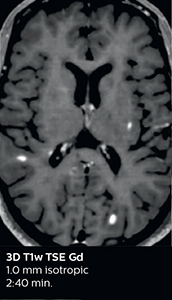

3D TSE T1w (with Compressed SENSE)

3D TSE T1w

1.0 x 1.0 x 1.0 mm*

2:10 min.